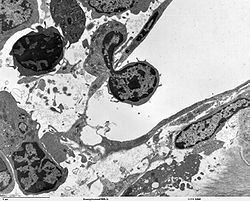

A transmission electron microscope image of an immune cell crossing from the bone marrow into the circulation

Inflammation is a particularly important and complex reaction to tissue injury, and is particularly important in fighting infection. Acute inflammation is generally a non-specific response triggered by the injured tissue cells themselves, as well as specialized cells of the innate immune system and previously developed adaptive immune mechanisms. A localized acute inflammatory response triggers vascular changes in the injured area, recruits pathogen-fighting neutrophils, and begins the process of developing a new adaptive immune response. Chronic inflammation occurs when the acute response fails to entirely clear the inciting factor. While chronic inflammation can lay a positive role in containing a continuing infectious hazard, it can also lead to progressive tissue damage, as well as predisposing (in some cases) to the development of cancer.